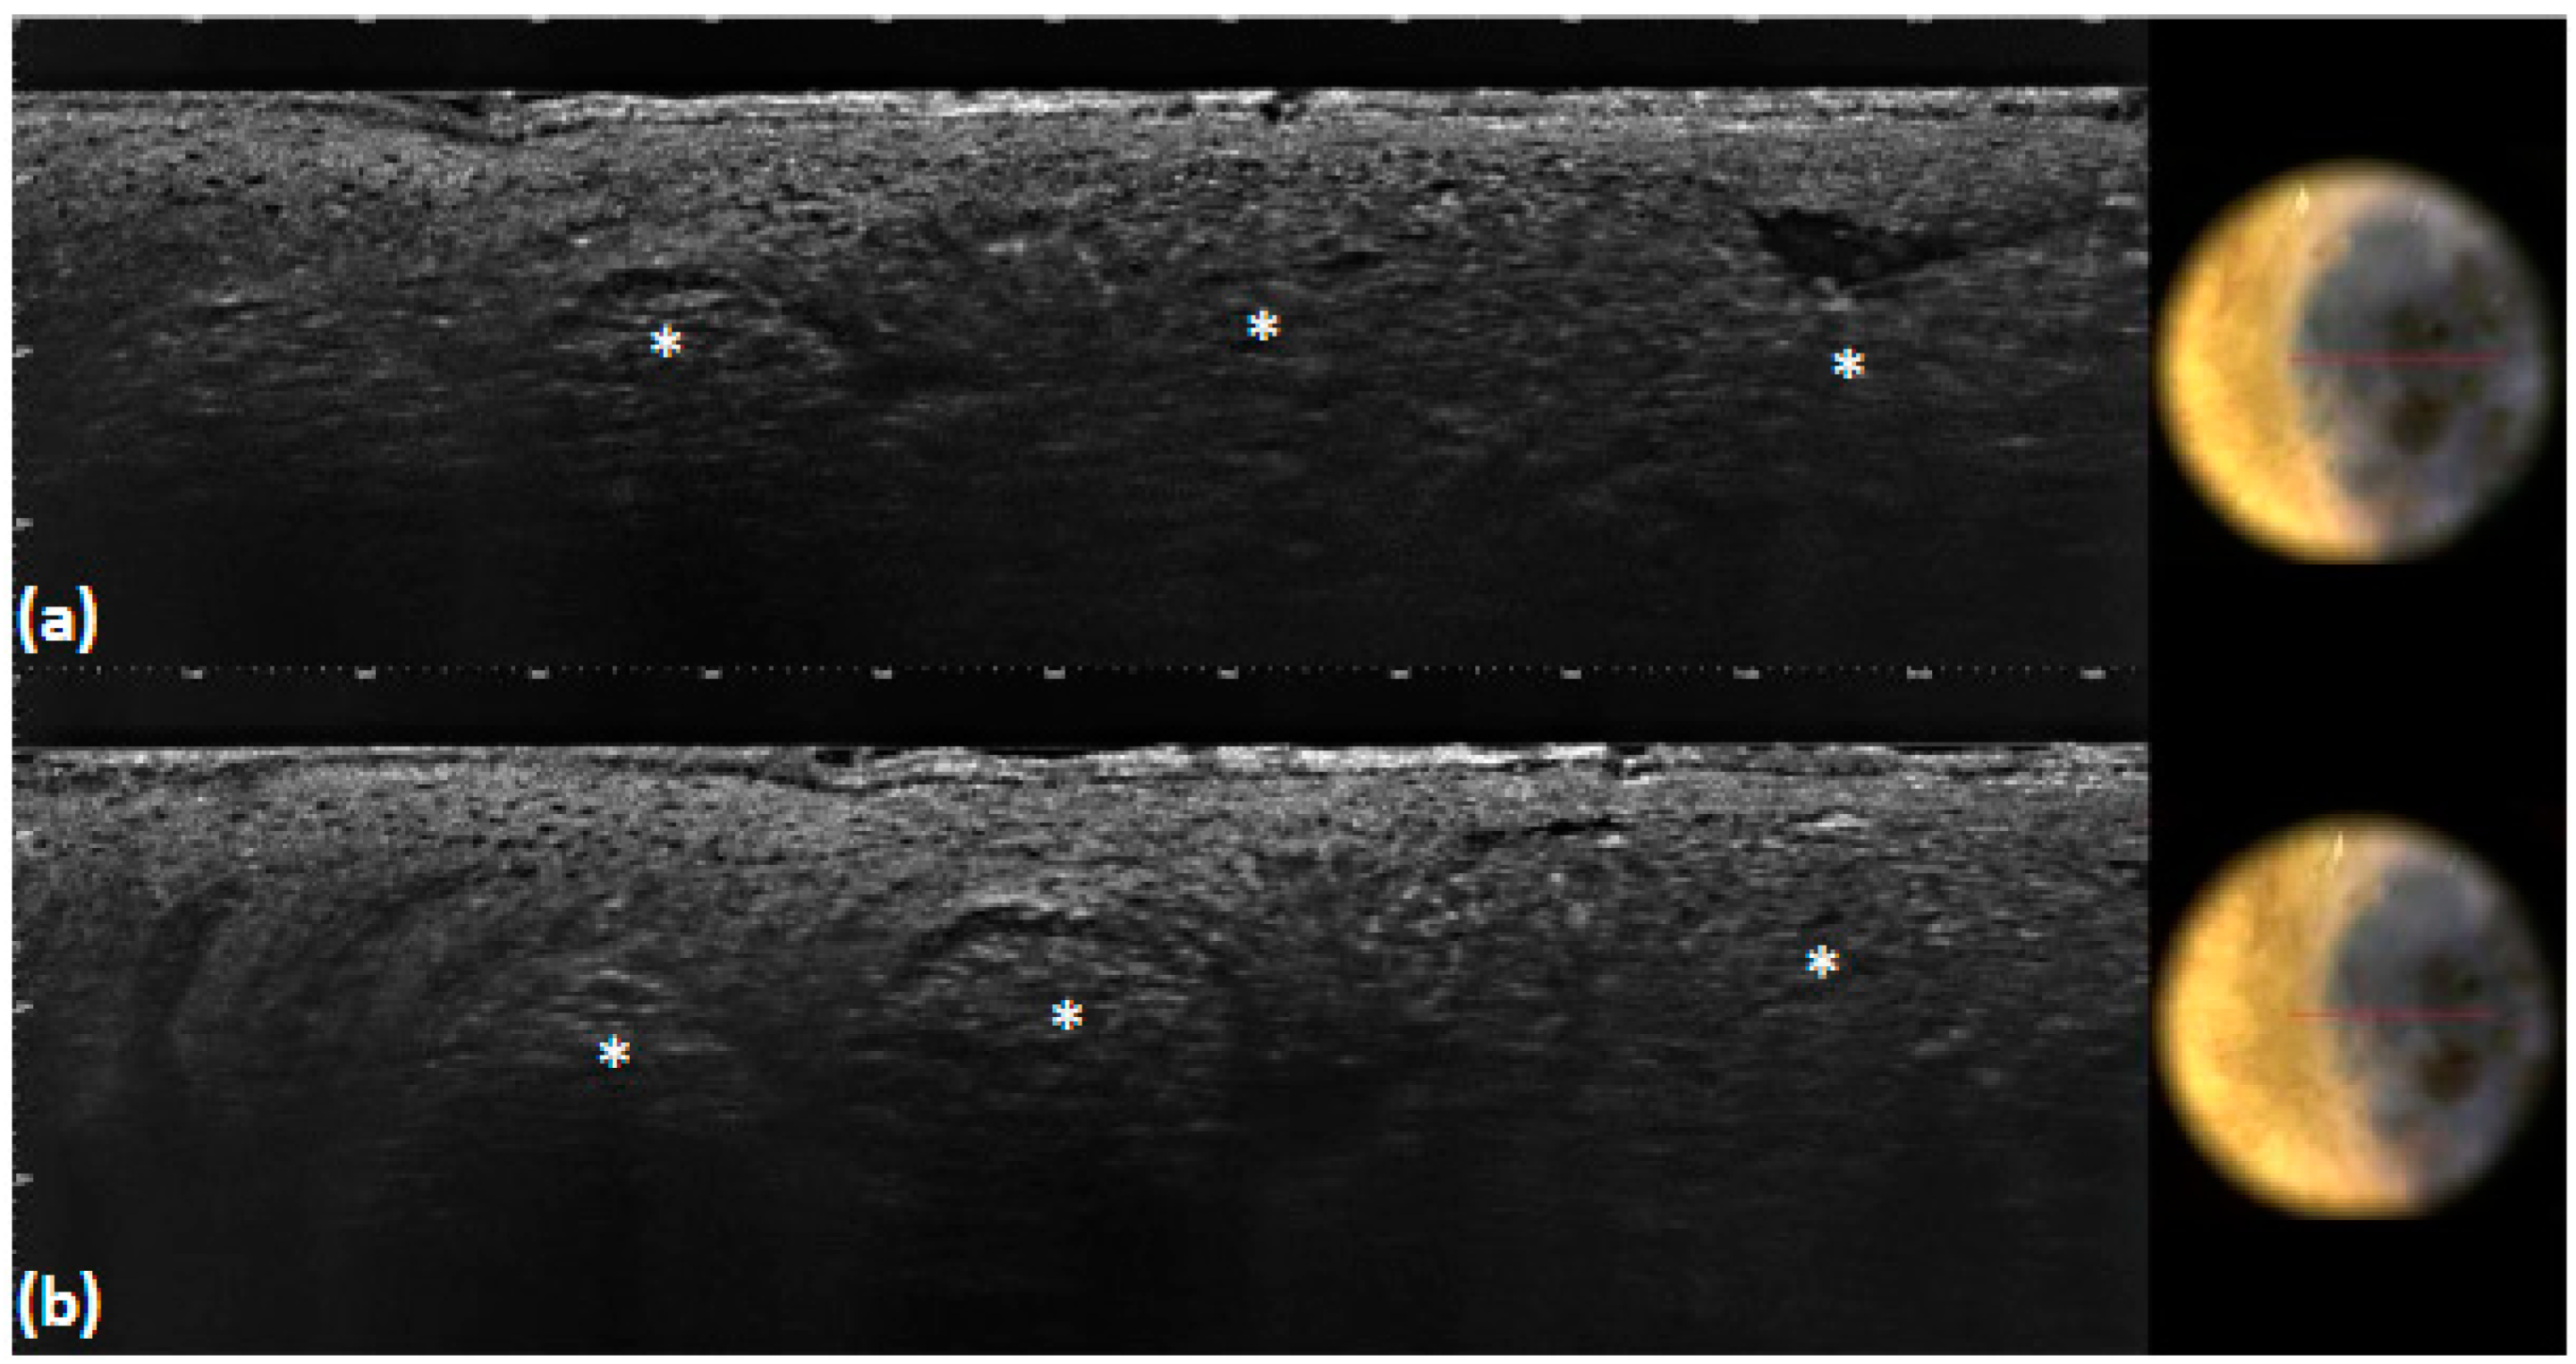

| Blue–gray globules | Roundish medium-reflective tumor lobules detached from the epidermis with variable hyper-reflective spots | 40 (40.0) | 36 (36.0) | 0.662 | 0.96 | 0.92 | <0.001 |

| Blue–gray ovoid nests | Medium-reflective tumor lobules detached from the epidermis with variable hyper-reflective spots | 10 (10.0) | 9 (9.0) | 1 | 0.99 | 0.99 | <0.001 |

| Multiple blue–gray dots | Hyper-reflective roundish small areas inside tumor lobules | 18 (18.0) | 13 (13.0) | 0.435 | 0.95 | 0.93 | <0.001 |